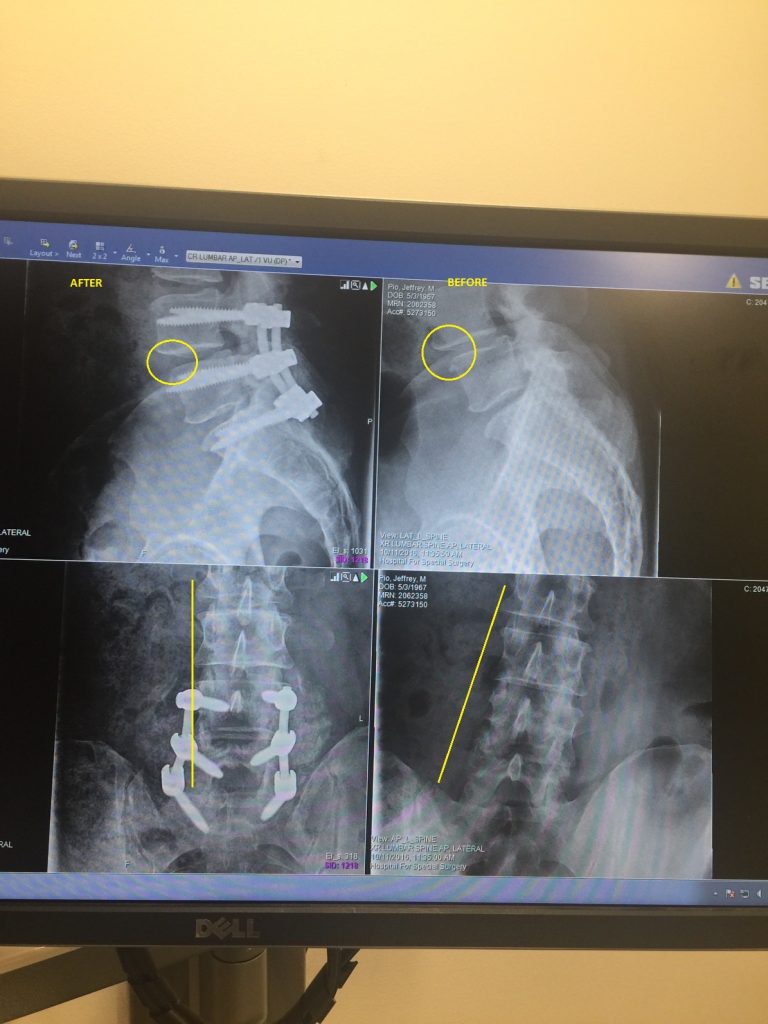

I began having lumbar pain and severe sciatica around 2009. At first I attributed it to piriformis syndrome and spent a lot of time stretching the muscle, but it never provided more than temporary relief. The pain gradually kept getting worse and I experimented with other treatment options such as physical therapy, meloxicam, acupuncture, chiropractors, inversion benches, and lumbar injections. I tried not to let the pain dictate my activities but the downside was that my posture and the way I walked began to change dramatically to compensate for the pain. My kids and any of their friends would comically imitate my unorthodox method of walking. Eventually I developed quite a severe curvature in my spine from compensating. I also wasn’t sleeping. It was ruining my relationships and my job. In 2016 I decided surgery might be necessary because I was also tripping a lot when my left ankle would give out, and my left leg would routinely go completely numb after a short walk or stand. I was initially able to get a referral to the fine people at HSS through my employer. After x-rays, MRI, and neurological testing, they were absolutely certain they knew the problem was stenosis and slipped vertebrae. The stenosis could not have been clearer on the MRI. I was told the muscle atrophy in my left leg would continue if I did nothing, but they were equally confident I was a good candidate for corrective surgery. I was nearly 50 years old and had never even had a minor operation in my life and was now contemplating a major surgery. I was terrified, but felt a lot of comfort in the confidence that Dr. Rawlins displayed on both knowing what the issue was and his ability to fix it. Right up to being wheeled into the operating room in Feb 2017 he gave me the option to change my mind. I am so pleased I did not. After a 5 hour surgery where he fused my L4-S1 and cleared the stenosis, I awoke in the recovery room, probably even more scared. However, when Dr. Rawlins visited me that evening I knew as soon as he touched my left foot that he corrected my back problem. I recalled it as clearly as my children being born. I was in the hospital for 5 days and could not have been in better care. The entire staff was excellent. Upon discharge I was immobile for days at home but soon began forcing myself to walk. Within a month I was walking up to 4 miles. Within 10 weeks I was on my boat and enjoying pain free days that I hadn't experienced in years. At 5 months I was wakeboarding again and knew that I had my life back - the life I had when I was 10 years younger. I can't emphasize enough how scared I was to have the surgery, particularly after reading all the negative stories that populate the internet. I now wish I would have done this 8 years ago. I just saw Dr. Rawlins for my 6 month checkup. I hope he realizes the gift he gives people. He has changed my life.